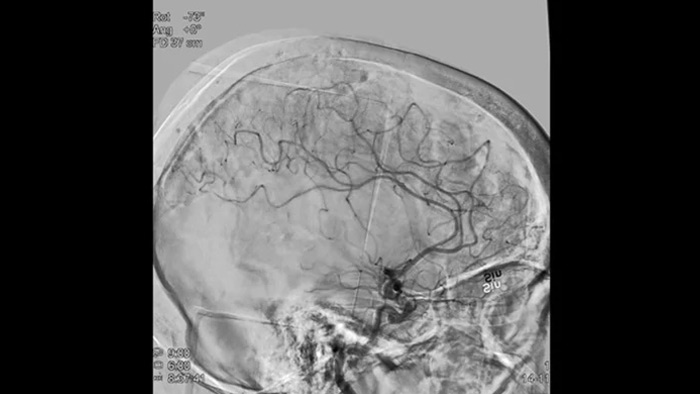

ASN 2D avec la technologie ClarityIQ

ClarityIQ applique la compensation automatique des mouvements lors de l’angiographie par soustraction numérique (ASN) en temps réel pour maintenir la netteté des images des vaisseaux et contribuer à une prise de décision fiable tout au long des procédures d’AVC.